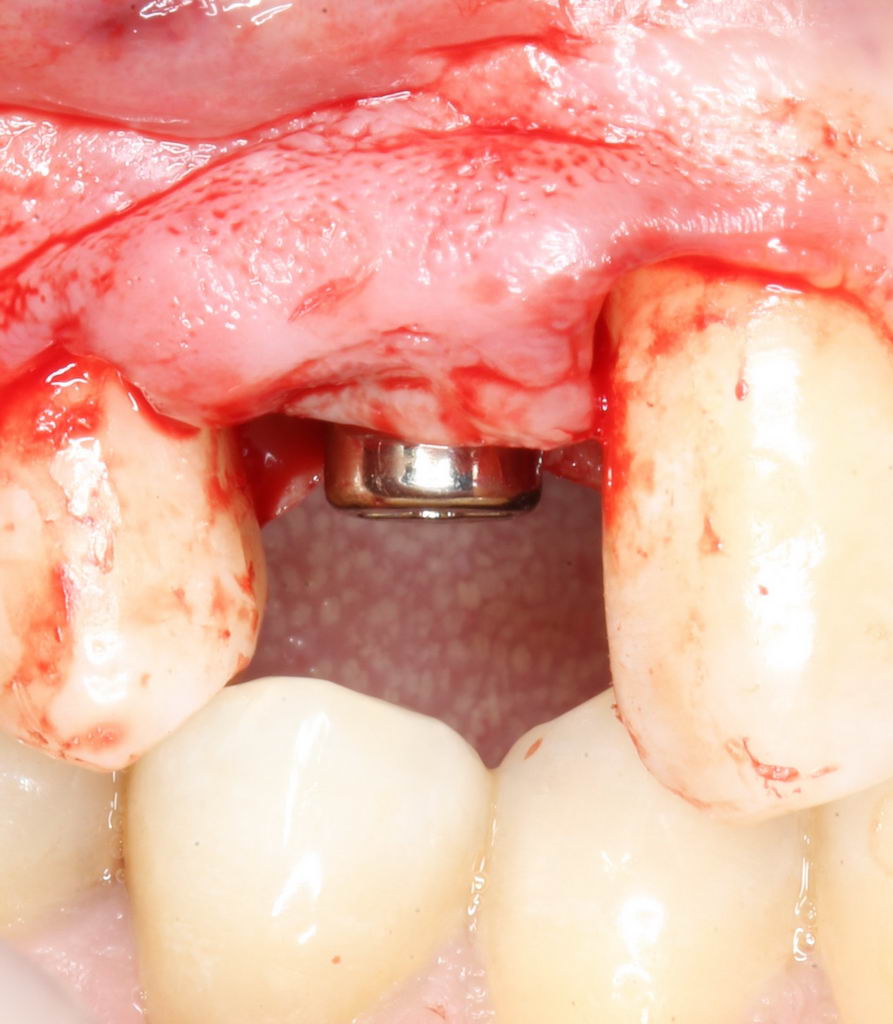

И, коль всё в порядке, переходим к следующему этапу операции — установке формирователя десны.

Установка формирователя десны.

Одномоментная установка формирователя десны позволяет сократить время и удешевить лечение — ведь по мере интеграции имплантата мы получаем нормально сформированный контур десны, готовый к установке протетической конструкции. Но это возможно лишь тогда, когда с объемами мягких тканей в области имплантата всё в порядке. То есть, как раз в нашем случае.

В CLINIC IN используют только одноразовые формирователи и только один раз:

С учётом клинических условий, мы подобрали к установленному имплантату формирователь Slim (без расширений) высотой 3 мм: